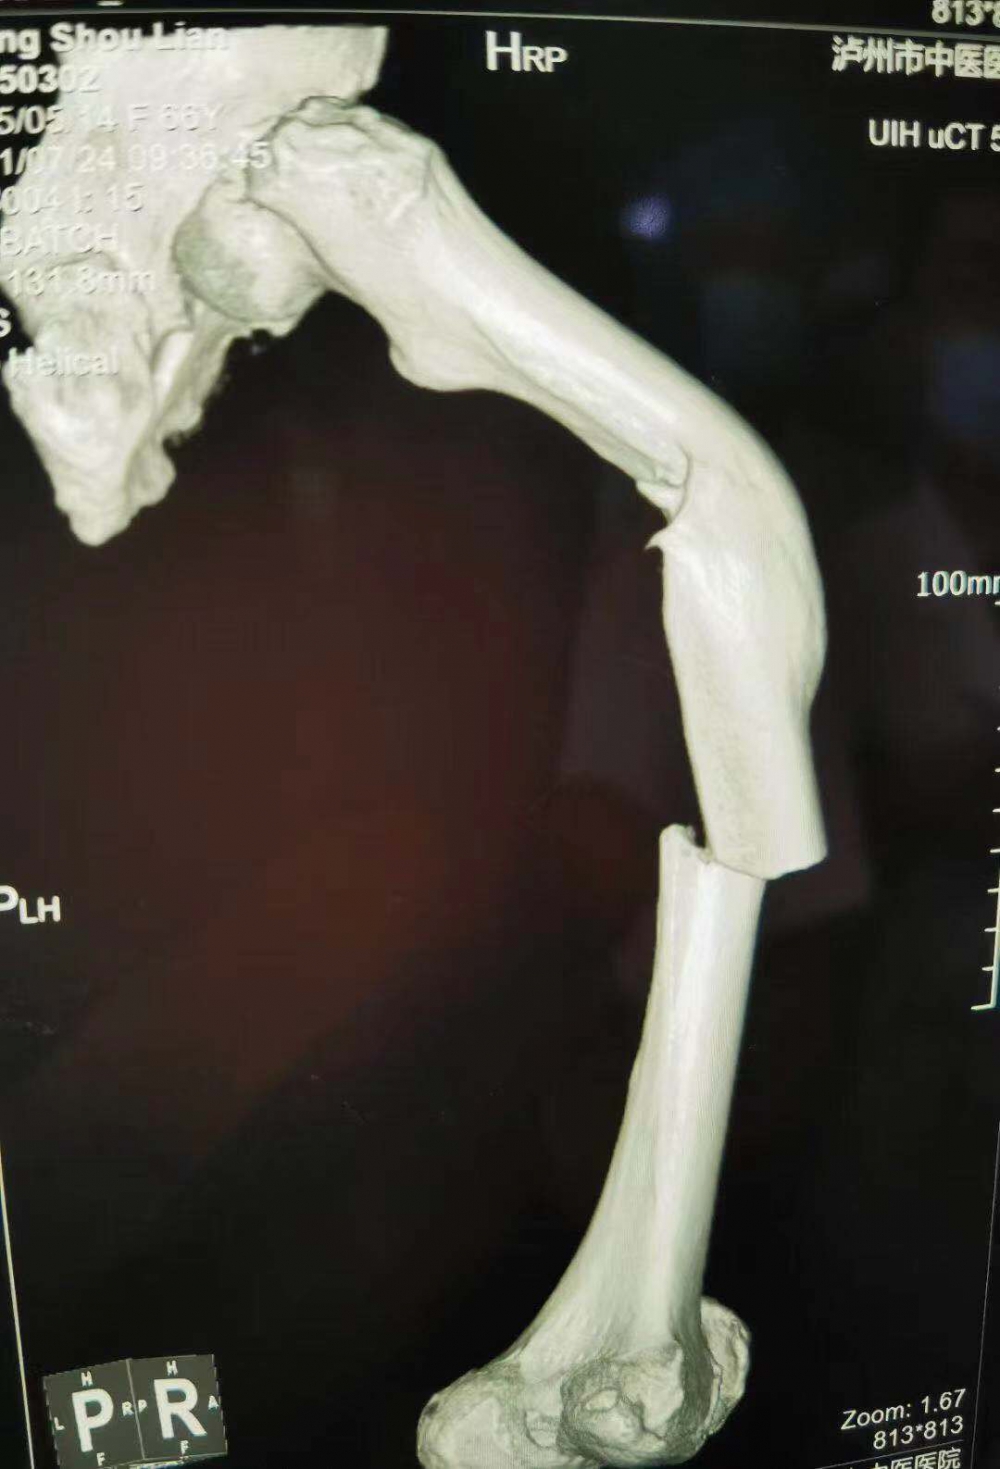

(股骨中段斷裂,上端有明顯畸形)

當(dāng)她的X光片出來(lái)時(shí),收治的醫(yī)生都被她的傷情嚇了一跳。原來(lái)此次她骨折的上端還有一處骨傷畸形愈合。這是什么情況呢?

原來(lái)張守蓮在三年前還摔傷過(guò)一次,當(dāng)時(shí)在一家醫(yī)院進(jìn)行了手法復(fù)位,但因操作不當(dāng),沒(méi)能復(fù)位成功,留下了后遺癥。三年來(lái)她都是以拄拐行走。